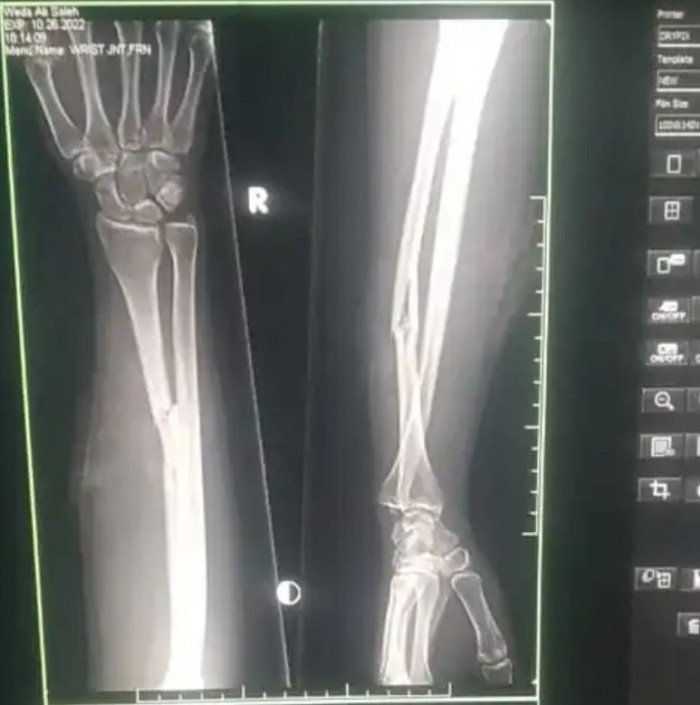

إصابة فتاة شمال الضالع بعيارين لقناص حوثي